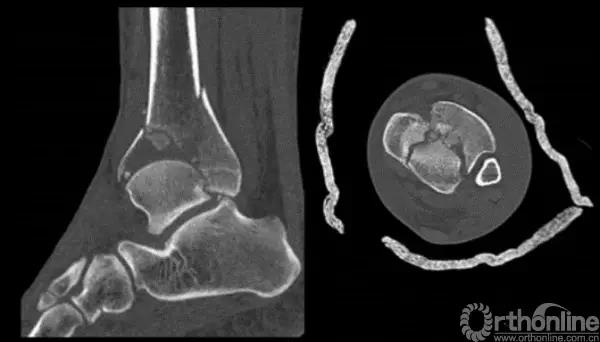

Pilon骨折为发生于胫骨远端并累及关节面,由垂直暴力合并或不合并扭转暴力导致的骨折,常表现为干骺端的压缩和关节面的粉碎。它是踝部的复杂骨折,以高能量损伤、不稳定、软组织损伤严重为特点。

Pilon骨折手术入路选择原则一般取决于最适合进行关节面复位的入路。cole在2013年jot发表的文章描述了pilon骨折的骨折线图根据多例病例汇总到一起,颜色越深则越骨折线经过的可能性越大。

他将pilon骨折大致的骨块进行了分类,分别为后、前内、前外三个骨折块。Pilon骨折的入路一共有5个,前内、前正中、前外、后内、后外。

1. 粉碎的骨折

针对该类骨折一般采取小块靠大块的原则,充分显露之后,先从后面开始,逐步把小块往大块上复位,逐渐复位到最前面。